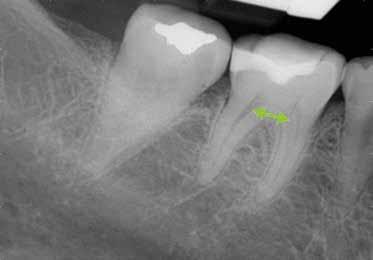

A 10 éves férfi páciens a felső frontfogai késői/nem megvalósuló előtörése miatt kereste fel a rendelőnket. A klinikai és a radiológiai vizsgálat során a jobb felső nagymetszőfog impakcióját észleltük (1. ábra). A fog horizontális tengelyállással és dilacerált gyökérrel rendelkezett. A felső dentális középvonal a fogak vándorlása miatt jelentős mértékben elcsúszott. A bal felső kismetszőfog is rendkívül kedvezőtlen pozícióba került.

1. a ábra: Az intraorális felvételen jól látható a jobb felső nagymetszőfog lehetséges impakciójára utaló foghiány.

1. b ábra: A panoráma röntgenfelvételen megfigyelhető a teljes impakcióban lévő jobb felső nagymetszőfog.

1. c ábra: A CBCT felvétel is igazolja a jobb felső nagymetszőfog impakcióját.